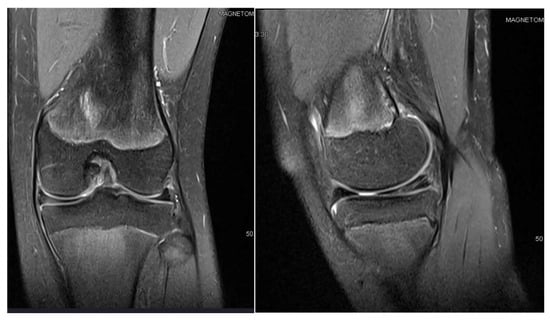

3.1. Case 1—P.E.